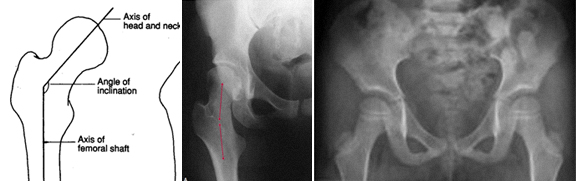

C - COXA VALGA

Quando houver sintomatologia (dor, claudicação) e alterações imagiológicas há indicação para cirurgia, para correção do valgo e para melhorar a congruência articular, diminuindo a sintomatologia e melhorando o bem-estar e qualidade de vida do paciente, e prevenindo a evolução e instalação da artrose grave.

A cirurgia deverá ser feita antes que haja artrose avançada.